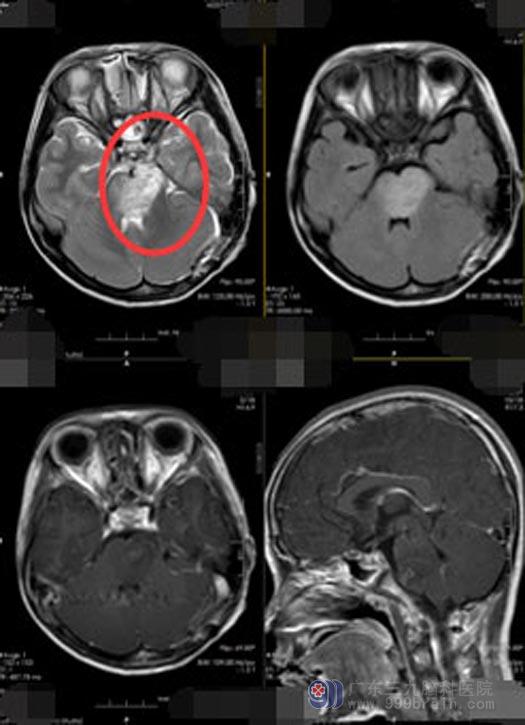

一向活泼乖巧的小梅从几天前开始就没精神,感觉右手和右脚没力气,而且吃啥吐啥。妈妈觉得入秋后天气多变,抵抗力容易下降, 11岁的孩子大概是感冒了。当地诊所医生没发现孩子有感冒症状,建议头部CT扫描,一检查还真发现了问题:脑干占位性病变,脑干明显肿胀,其内周围有块状占位性病变,显示高低混杂信号,包绕基底动脉,最大层面病状范围4.6cm×3.0cm,四脑室受压明显。

进一步的检查后,鲁明副院长初步判断孩子是脑干肿瘤伴脑干出血、吸入性肺炎,需要及时手术治疗。术中显微镜下切开硬脑膜,钩开左侧小脑半球,见左侧的桥小脑角灰白,质软肿瘤组织,切除桥小脑角区肿瘤,对周边的大血管及神经系统保护良好,术程顺利。术后复查CT,无出血,无水肿加重。